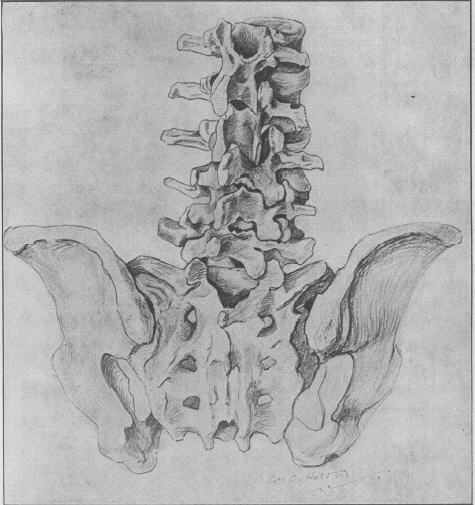

1911年3月16日

Joel E. Goldthwait详细描述了一例背痛病例,在手术过程中没有发现明显异常。他怀疑是腰骶关节与椎间隙产生移位和椎间盘的脱出,后者压迫神经根和脊髓。他认为,治疗这个疾病必须把腰椎间盘部分或全部切除。